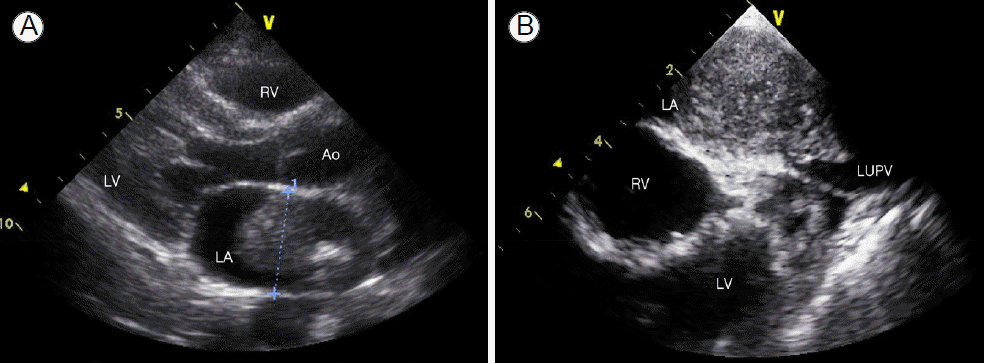

심초음파 소견: 좌심방 후벽 거의 전체를 뿌리로 하여 좌상부 폐정맥까지 자라난 직경 54 mm의 고에코상 종괴가 발견되었다. 종괴로 인해 발생한 경도의 승모판 역류(grade 2)와 좌상부 폐정맥의 완전 폐색이 동반되어 있었다(Fig. 1).

Figure 1.

(A) Transthoracic and (B) transesophageal echocardiograms demonstrating a large, immobile left atrial mass extending from the LA posterior wall to the left pulmonary vein with LUPV occlusion. Left, parasternal long-axis view. Ao, aorta; LA, left atrium; LV, left ventricle; RV, right ventricle; LUPV, left upper pulmonary vein.